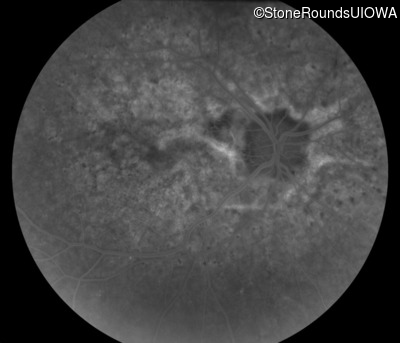

Fluorescein Angiography - Right - 20/20 -1

Exemplar